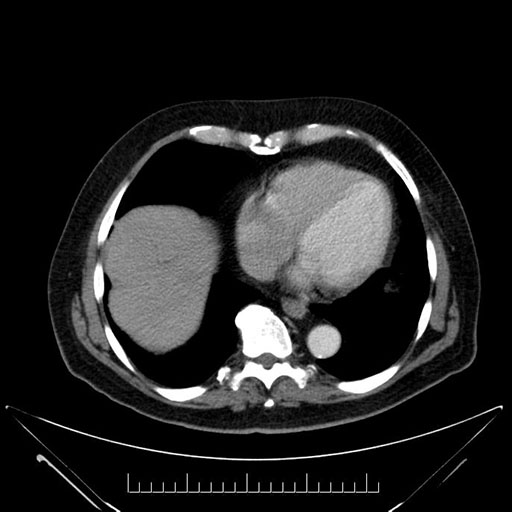

Imaging Analysis

Look through the patient's CT scan to identify any areas of concern for the necessary procedure.

Based on your CT findings, which issue(s) would give reason for "planned slowing down moment(s)" in this case?

Considering a standard Whipple procedure, what step(s) of the operation would you do differently in this case?